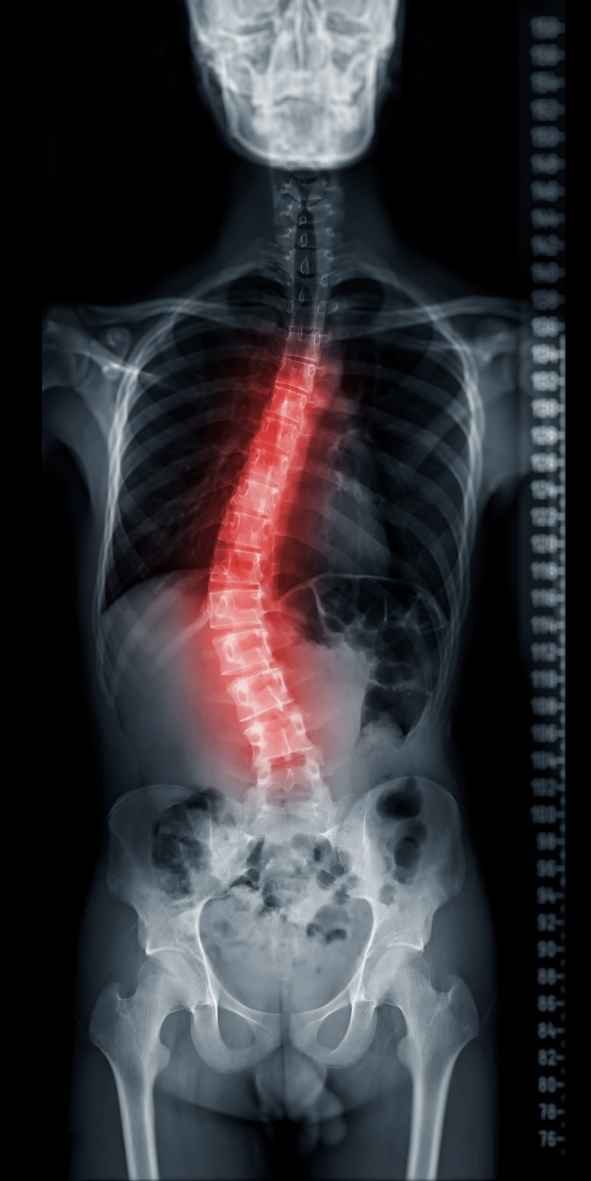

A escoliose é uma condição ortopédica que afeta a coluna vertebral, apresentando uma curvatura anormal que é acompanhada pela rotação…